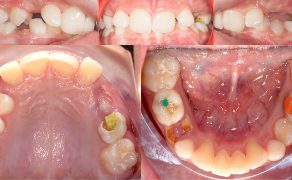

Cel. Celem pracy jest opis terapii ortodontycznej i czynnościowej pacjenta w późnym okresie uzębienia mlecznego, u którego rozpoznano: II klasę zębową i szkieletową podgrupy 2, brachycefaliczny typ wzrostu z wklęsłym profilem, ekstruzją górnych siekaczy centralnych i wychyleniem siekacza bocznego szczęki, nadmiernym napięciem mięśni żwaczy, parafunkcją zaciskania zębów i brakiem miejsca na stałe kły górne.

Opis przypadku. Artykuł opisuje leczenie 11-letniego pacjenta w późnym okresie uzębienia mlecznego, u którego rozpoznano: II klasę zębową i szkieletową podgrupy 2, brachycefaliczny typ wzrostu z wklęsłym profilem, ekstruzją górnych siekaczy centralnych i wychyleniem siekacza bocznego szczęki. W leczeniu zastosowano płytkę górną Schwarza ze śrubą trójkierunkową oraz urządzenie odciążające MFS złożone z relaksatora mięśniowego i płytki nagryzowej. Urządzenie odciążające jest efektywnym uzupełnieniem terapii ortodontycznej, wymusza długotrwałą pożądaną w terapii pracę mięśni zespołu ustno-twarzowego.